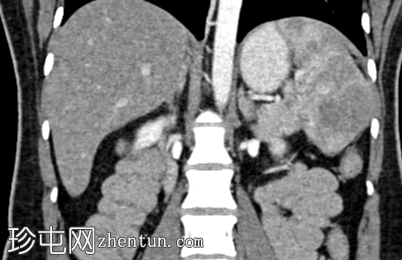

冠状位增强扫描

动脉期

脾脏内可见一圆形低密度病灶,动脉期呈周边环状强化,延迟期呈轻微向心性充盈

学特征为:病灶周围呈放射状强化,中心呈放射状强化,周围环状强化,中心充盈轻微。增强扫描后可见中央星状瘢痕。